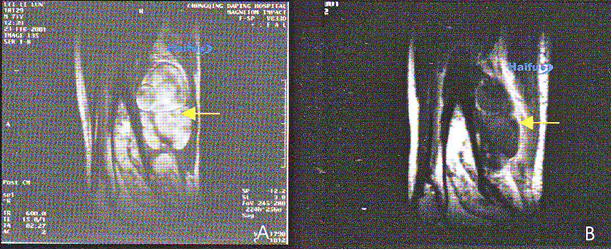

9. МРТ с контрастированием гандолинием 71-летнего пациента с мягкотканой саркомой бедра.

А) Сагиттальный срез до HIFU. В опухоли отчетливо визуализируется интенсивное накопление контрастного вещества (стрелка). В) через 2 недели после HIFU. В пролеченной зоне контрастное вещество не накапливается (стрелка), что означает наличие коагуляционного некроза ткани опухоли.